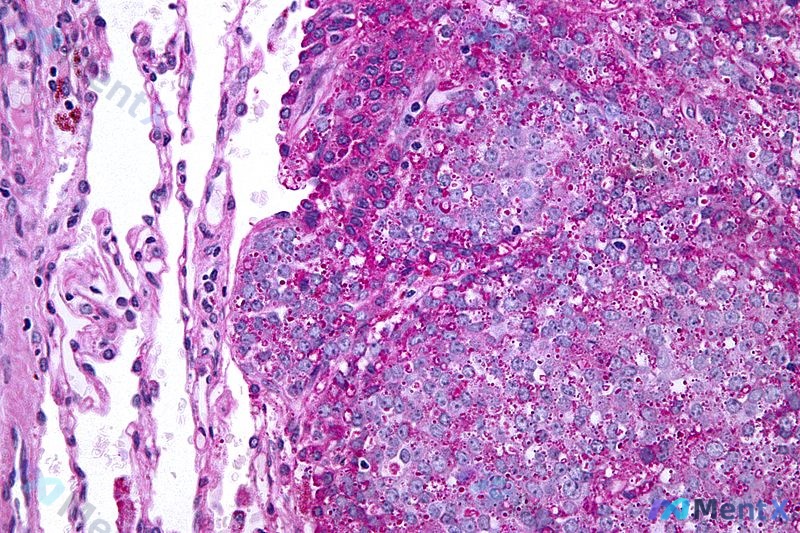

看到这个很典型的病例,整理了一下完整资料和分析思路分享给大家。 病例基本信息 - 患者:24岁青年男性 - 主诉:近1个月内两次直肠出血就诊 - 既往史:无严重疾病史,未服用药物,不吸烟 - 家族史:父亲42岁时因结肠癌去世 - 体征:生命体征正常;右下颌骨可触及一个无压痛、固定于骨的小硬块;腹直肌...